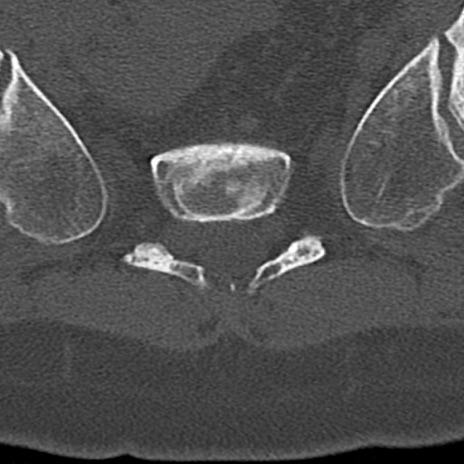

腰椎CT

横断像と矢状断像